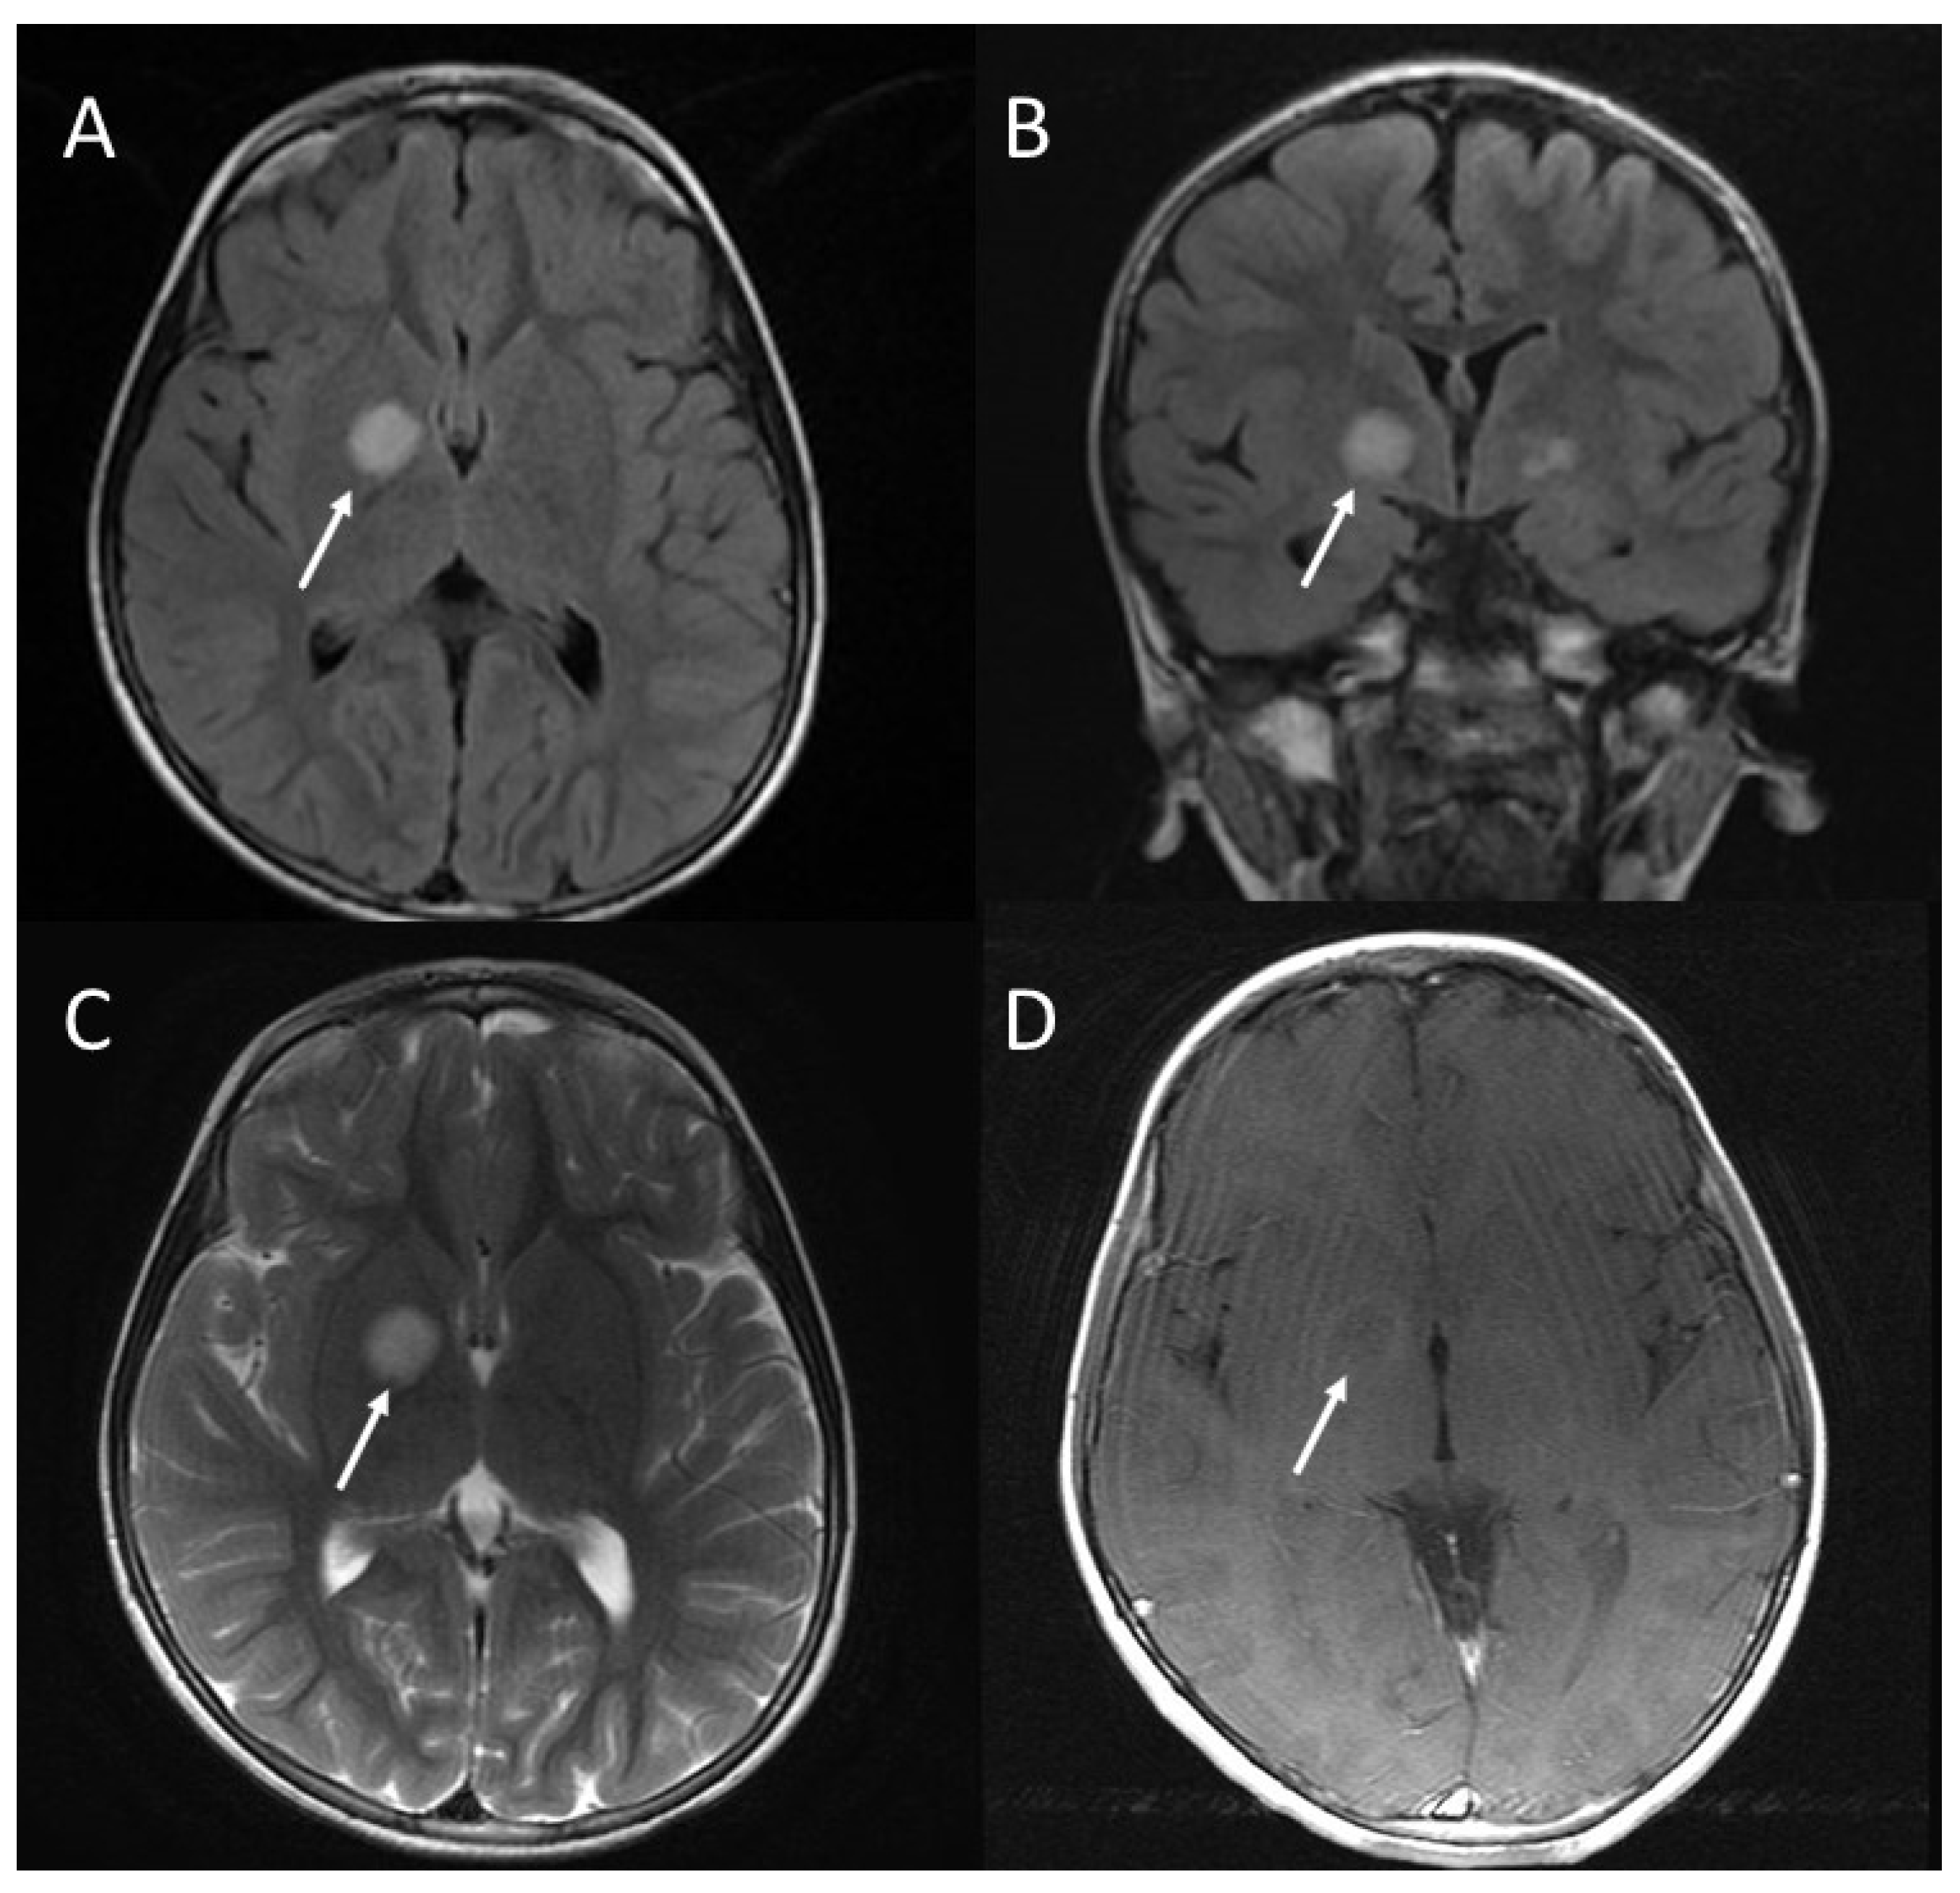

2.3. Brain Abnormalities: UBOs or FASI

| Brain abnormalities: UBOs or FASI | 43–93% | Areas of increased signal intensity on T2-weighted MRI sequence, not visualized on T1-weighted images and do not show mass effect or contrast enhancement; |

| Rarely seen in patients older than 20 years; | ||

| The cerebellum, the brainstem, and the basal ganglia are the regions most involved. | ||